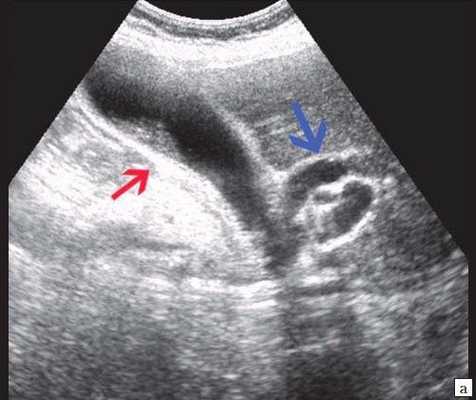

Рис. 1. Ультразвуковая картина билиарной гипертензии при механической желтухе.

а) Расширенные внутрипеченочные протоки.

б) Увеличенный желчный пузырь с густой взвесью (красная стрелка) и расширенный ОЖП (синяя стрелка).

а) Увеличенный желчный пузырь с густой взвесью внутри (красная стрелка) и расширенный ОЖП (синяя стрелка).

б) Расширение внутрипечоночных протоков (синяя стрелка).